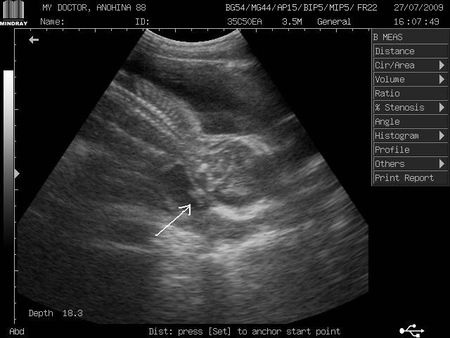

Были вчера с нашим папой на узи.Он первый раз, поэтому восторгов было очень много :)))) Каждые пять секунд спрашивал врача - это он пошевелился,да?! :) Посчитали пальчики, померили все что надо - с малышом все отлично, все показатели в норме!!

А вот под конец меня огорчили.Точнее сказать очень напугали.Врач увидел открытие внутреннего зева на 1 см!!!!!

Правда при этом шейка 4 см, и вообще он сказал что такое видит очень часто и это совершенно нормально.Сказал не думать даже и не стал заносить в заключение.Написал просто "Шейка матки и церв.канал без особенностей".........Мне потом вечером уже стало казаться что у меня живот болит - нервное видать:( Сегодня ттт все ок.Но теперь вот сижу и не знаю, бежать к врачу, или ждать планового приема (еще 3 недели)...Так то врач этот очень уважаемый в городе,его мнение достаточно веское....